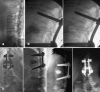

Cement reinforcement for the treatment of osteoporotic vertebral fractures is efficient mean with high success in pain release and prevention of further sintering of the reinforced vertebrae; however, the technique does not allow to address the kyphotic deformity. Kyphoplasty was designed to address the kyphotic deformity and help to realign the spine. It involves the percutaneous placement of an inflatable bone tamp into a vertebral body. Restoration of VB height and kyphosis correction is achieved by inflation of the bone tamp with liquid. After deflation, a cavity is created that eases the cement application. The potential of kyphosis reduction is given in fresh fractures with a range of 0-90% for height restoration and absolute correction of the kyphotic angle of 8.5 degrees. The cavity formation, on one hand, and the different cementing technique leads to lower risk for cement extravasation. An alternative method for kyphosis correction represents the so-called lordoplasty where the adjacent vertebrae are reinforced first and with the cannulas in place acting as a lever the reduction of the collapsed vertebra can be performed. The results with respect to kyphosis correction are superior in comparison with a kyphoplasty procedure.